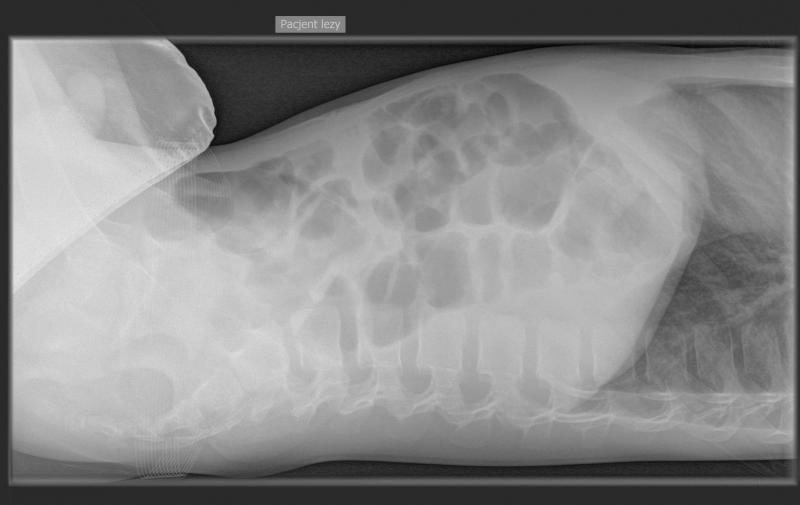

Przypadek 4: 11-letni chłopiec z napadowymi bólami brzucha od 3 tygodni, z wielokrotnymi wymiotami. Pacjent ani rodzice nie potrafili określić kiedy było ostatnie wypróżnienie. Podejrzenie niedrożności przewodu pokarmowego.

Rozpoznanie: Liczne poziomy płynu w dystalnych pętlach jelita cienkiego oraz w miernie rozdętym jelicie grubym do wysokości zstępnicy, brak powietrza w rzucie odbytnicy - cechy niedrożności. Bez cech perforacji.